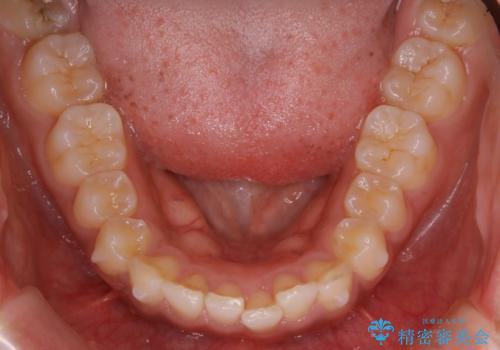

インビザライン矯正 歯を抜かずに出っ歯を改善!

- 出っ歯と前歯の隙間が空いていることを気にされて来院されました。

また、自然な感じで口元を下げていとのことでした。

奥歯のかみ合わせが問題なかったため、上顎の前歯の隙間を閉じるとともに、上顎の歯の側面を削ることをメインにして、出っ歯を改善する治療計画としました。

上顎の歯の傾きを変えるうえで、下顎の歯とのバランスのことも考え、下顎の歯の側面も削ることを加えています。

また、今回は口元を変えたい中に、劇的な変化は避けたいとのことだったので、抜歯をしない計画としています。

抜歯をしない場合、口元の変化は感じにくいですが、前歯の傾きが変わることで、口の閉じやすさは感じていただけたとのことです。

症例にもよりますが、本症例は奥歯のかみ合わせに問題がなかったので歯の側面を削ることメインに、前歯の傾きを改善することができました。

抜歯を行う場合や抜歯をしなくても奥歯の位置をずらす場合は、治療期間が長期化することが多いですが、今回は歯を削ることで改善できたため、短期間で治療を完了することができました。